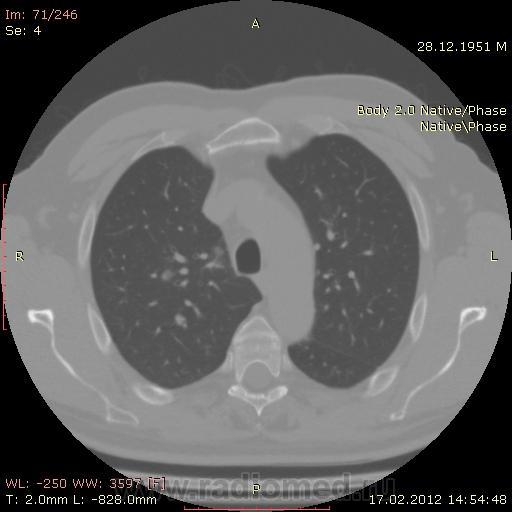

КТ.

В феврале 2012 года при очередном флюрографическом обследовании были обнаружены изменения в лёгких. По собственной инициативе было сделано КТ лёгких.

Одну почку (левую) удалили по причине светло-клеточного рака.

Повторяюсь (мнение озвучил еще до КТ и до Ваших коментов) но это отдаленные по времени метастазы рака почки....увы....и даже если будет найден еще один первичный очаг, то все равно это - метастазы...опять - увы....